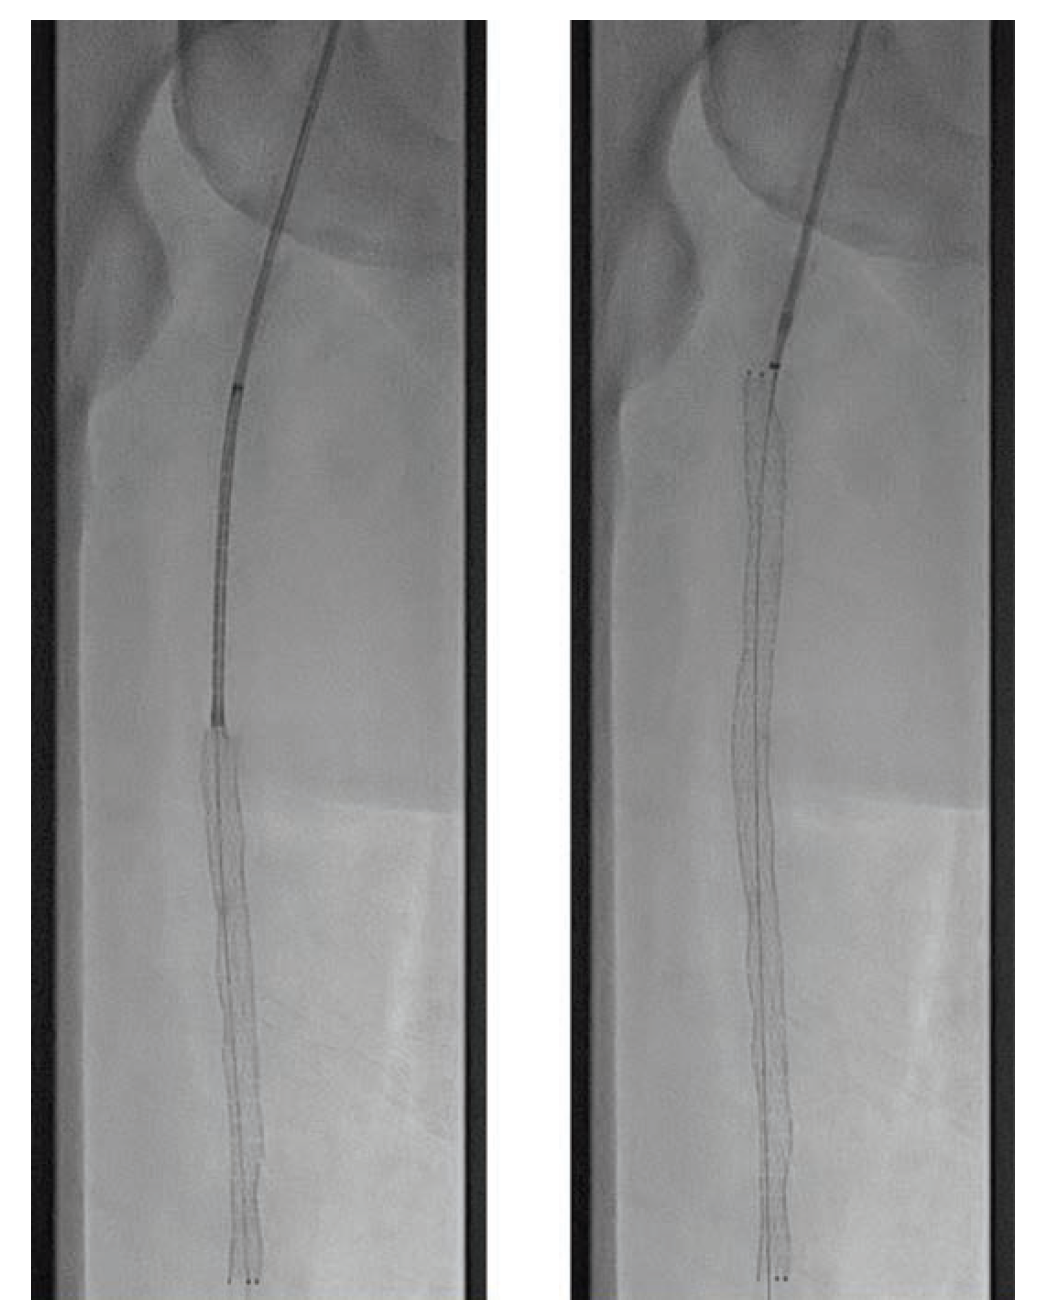

A 70-year-old man was referred for consideration of right lower extremity (RLE) intervention after initially presenting with resting ischemic pain and early tissue necrosis of the metatarsals, consistent with critical RLE ischemia. The patient was taken to the catheterization lab, where contralateral left common femoral artery (CFA) access was gained using a Micropuncture needle (Cook Medical) under ultrasound guidance. A 6F, 11 cm arterial sheath was placed into the artery over a guidewire. The right common iliac artery was engaged using a 5F internal mammary artery catheter; a 0.035" stiff-angled Glidewire (Terumo Interventional Systems) was then advanced to the right CFA. Peripheral angiography of the RLE was performed, demonstrating a total occlusion of the superficial femoral artery (SFA) as well as total occlusion of the popliteal artery and all three infrapopliteal vessels (Figure 1 and Figure 2). The 6F sheath was then exchanged over the Glidewire for a 6F, 45 cm sheath. At this time, anticoagulation was initiated with intravenous unfractionated heparin at 80 units/kg to achieve an activated clotting time (ACT) > 250 seconds.